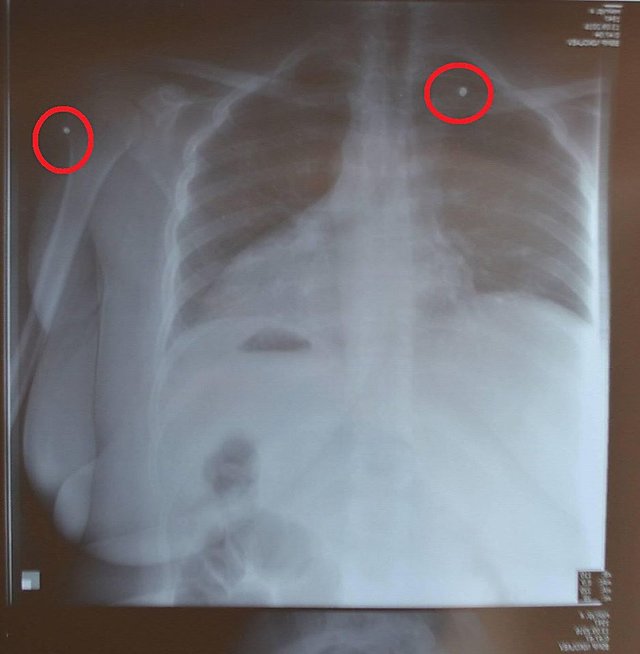

В Николаеве в ночь на 13 сентября местная жительница Анжелика Майгур получила два ранения дробью, когда она находилась на балконе своей квартиры.

По словам Майгур, происшествие случилось около 23:25. Судя по комментариям женщины в соцсети, ее соседи ночью «устроили разборки», в ходе которых она получила две раны дробью – в шею и в плечо.